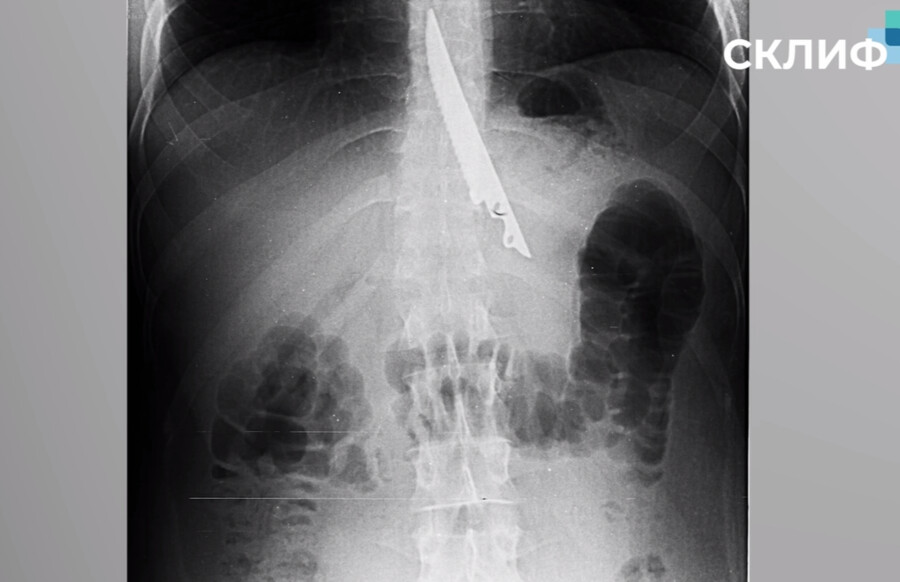

В Москве врачи чудом спасли мужчину, который случайно проглотил нож, сообщили в пресс-службе НИИ имени Склифосовского. Инцидент произошел, когда мужчина в компании друзей на отдыхе жарил шашлык.

Он подавился куском мяса, а его окружение не придумало ничего лучше, как протолкнуть еду 20-сантиметровым ножом. В итоге шашлычник случайно проглотил острый предмет. Врачи Склифа извлекли его, проведя операцию.